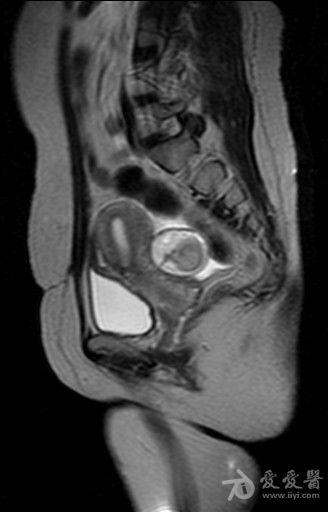

体检发现盆腔包块入院检查(较典型病例MRI平扫加增强)。

病史如题。图像如下。 T2

含有脂质信号,边缘清楚,考虑畸胎瘤